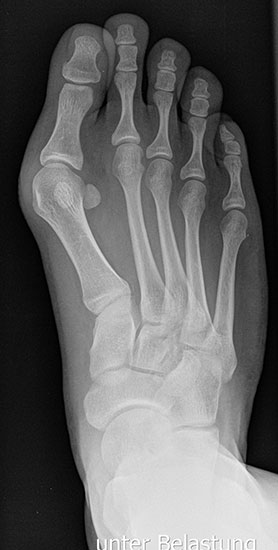

Bei einem juvenilen Hallux valgus handelt es sich um eine schon im Kindes – oder Adoleszentenalter 1 bestehende Valgusdeviation der großen Zehe bei Spreizfuß mit vergrößertem Intermetatarsalwinkel I / II aufgrund einer Adductionsstelllung des Metatarsale I – Metatarsaus primus varus.

Im Gegensatz zum Hallux valgus des Erwachsenen ist die Valgusabweichung der großen Zehe meist geringer ausgeprägt als bei Erwachsenen, der Intermetatarsalwinkel oft stark vergrößert. Die Angaben ab wann der Intermetatarsalwinkel als vergrößert gilt schwanken zwischen > 9° 2 und >14°3. Das Ausmaß der Beschwerden korrelieren nicht mit dem Auftreten und dem Schweregrad der Deformität (Zollinger 1990, Zollinger 1993). Begünstigend wirkt eine Schrägstellung des ersten Tarsometatasalgelenkes (Hefti 1998) und eine Hypermobilität dieses Gelenkes 2 in Kombination mit einer Bindegewebsschwäche. Häufig liegt eine positive Familienanamnese vor. In einer Untersuchung von Coughlin fand sich eine Vererbung über die mütterliche Linie in 72%, ein milder bis stark ausgeprägter Knick-Senkfuß in 17% (das entspricht der Quote von Knick-Senkfüßen in der Normalbevöl­kerung) aber in 22% ein Pes adductus, das ist wesentlich mehr als in der Normalbevölkerung zu erwarten wäre 4. Auch für Hefti (1998) gilt der Pes adductus als Komponente des Sichelfußes als begünstigend. Zur Inzidenz des Hallux valgus juvenilis finden sich je nach Autor verschiedene Angaben. Nach Auswertung von Schuluntersuchungen liegt die Häufigkeit zwischen 1,6 % bis 17% 56. Häufig tritt die Fehlstellung doppelseitig auf. Der Anteil der betroffenen Mädchen liegt 4-5x höher als bei Jungen (Lamprecht 2015).

Röntgen

Standard ist die belastete Röntgenaufnahme des Fußes dorso-plantar und seitlich. Günstig ist eine Röhrenkippung von 10°-20°, um die Gelenke der Lisfranc-Linie einsehen zu können.

• Hallux valgus Winkel

• Intermetatarsalwinkel I zu II

• Pes metatarsus adductus

Tabelle 1: Normwerte der Winkelmaße

Intermetatarsalwinkel Hallux valgus Winkel

Normalwerte < 10° < 20°

Leichte –mittelgradige Fehlstellung 10°- 16° 20°- 40°

Schwere Fehlstellung > 16° > 40°